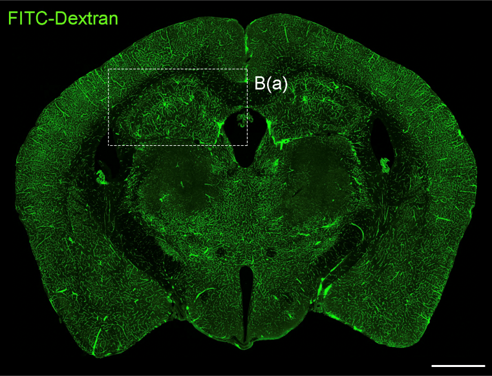

뇌혈관장애 및 퇴행성뇌질환 개선연구

- 연구주제 : 뇌혈관장애-유래 인지기능 저하 및 근감소증 제어기전 연구

- 연구주제 : 뇌경색 동물모델 구축을 통한 뇌혈관 장애 및 염증제어 후보물질 발굴